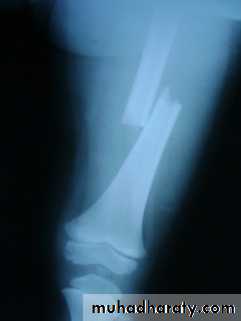

Femoral shaft fracture

This fracture occurs at any age, it is common especially in young adults, and usually results from a high energy injury, such as

( car accident , fall from height).

X-ray :

Shows the type of fractures, and displacement. The x-ray should include the hip and knee and x-ray of pelvis to avoid missing segmental fractures, knee injuries, fractures of neck of femur, dislocation of hip, fractures of acetabulum and pelvis.